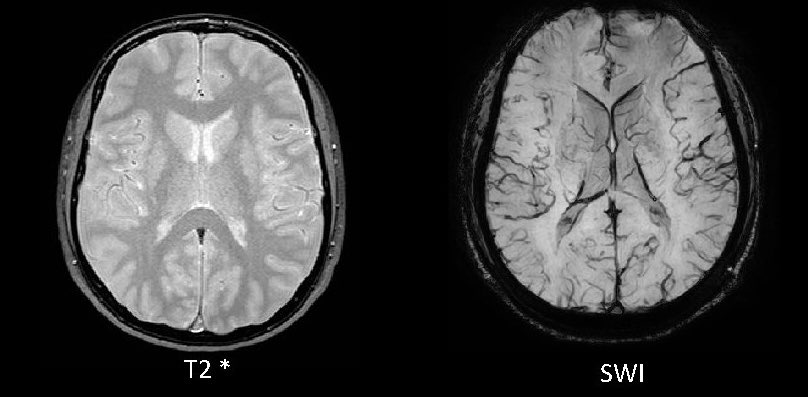

4. GRE/SWI/SWAN/T2*: helps to distinguish nuances among entities on your differential.

in general, abnormal = dark (blood, vascularity, &c; abscesses tend to have dark rims on SWI)